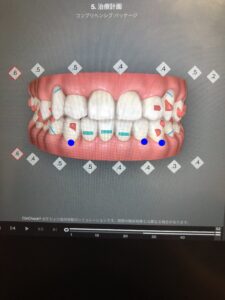

10枚目のアライナーを付ける頃にはこんな歯並びに。

正面からは変化しているように見えませんが、角度を変えてみると奥歯の辺りに隙間ができているのがわかります。

20枚目も、正面だと変化がわかりにくいですが、下から見ると隙間のある箇所が変わっているのがわかります。

30枚目になると、ようやく正面からでも変化がわかるようになりました。